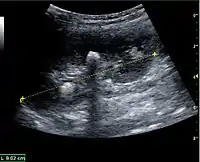

Figure 6. Complex cyst with thickened walls and membranes in the lower pole of an adult kidney. Measurements of kidney length and the complex cyst on the US image are illustrated by '+' and dashed lines.[1]